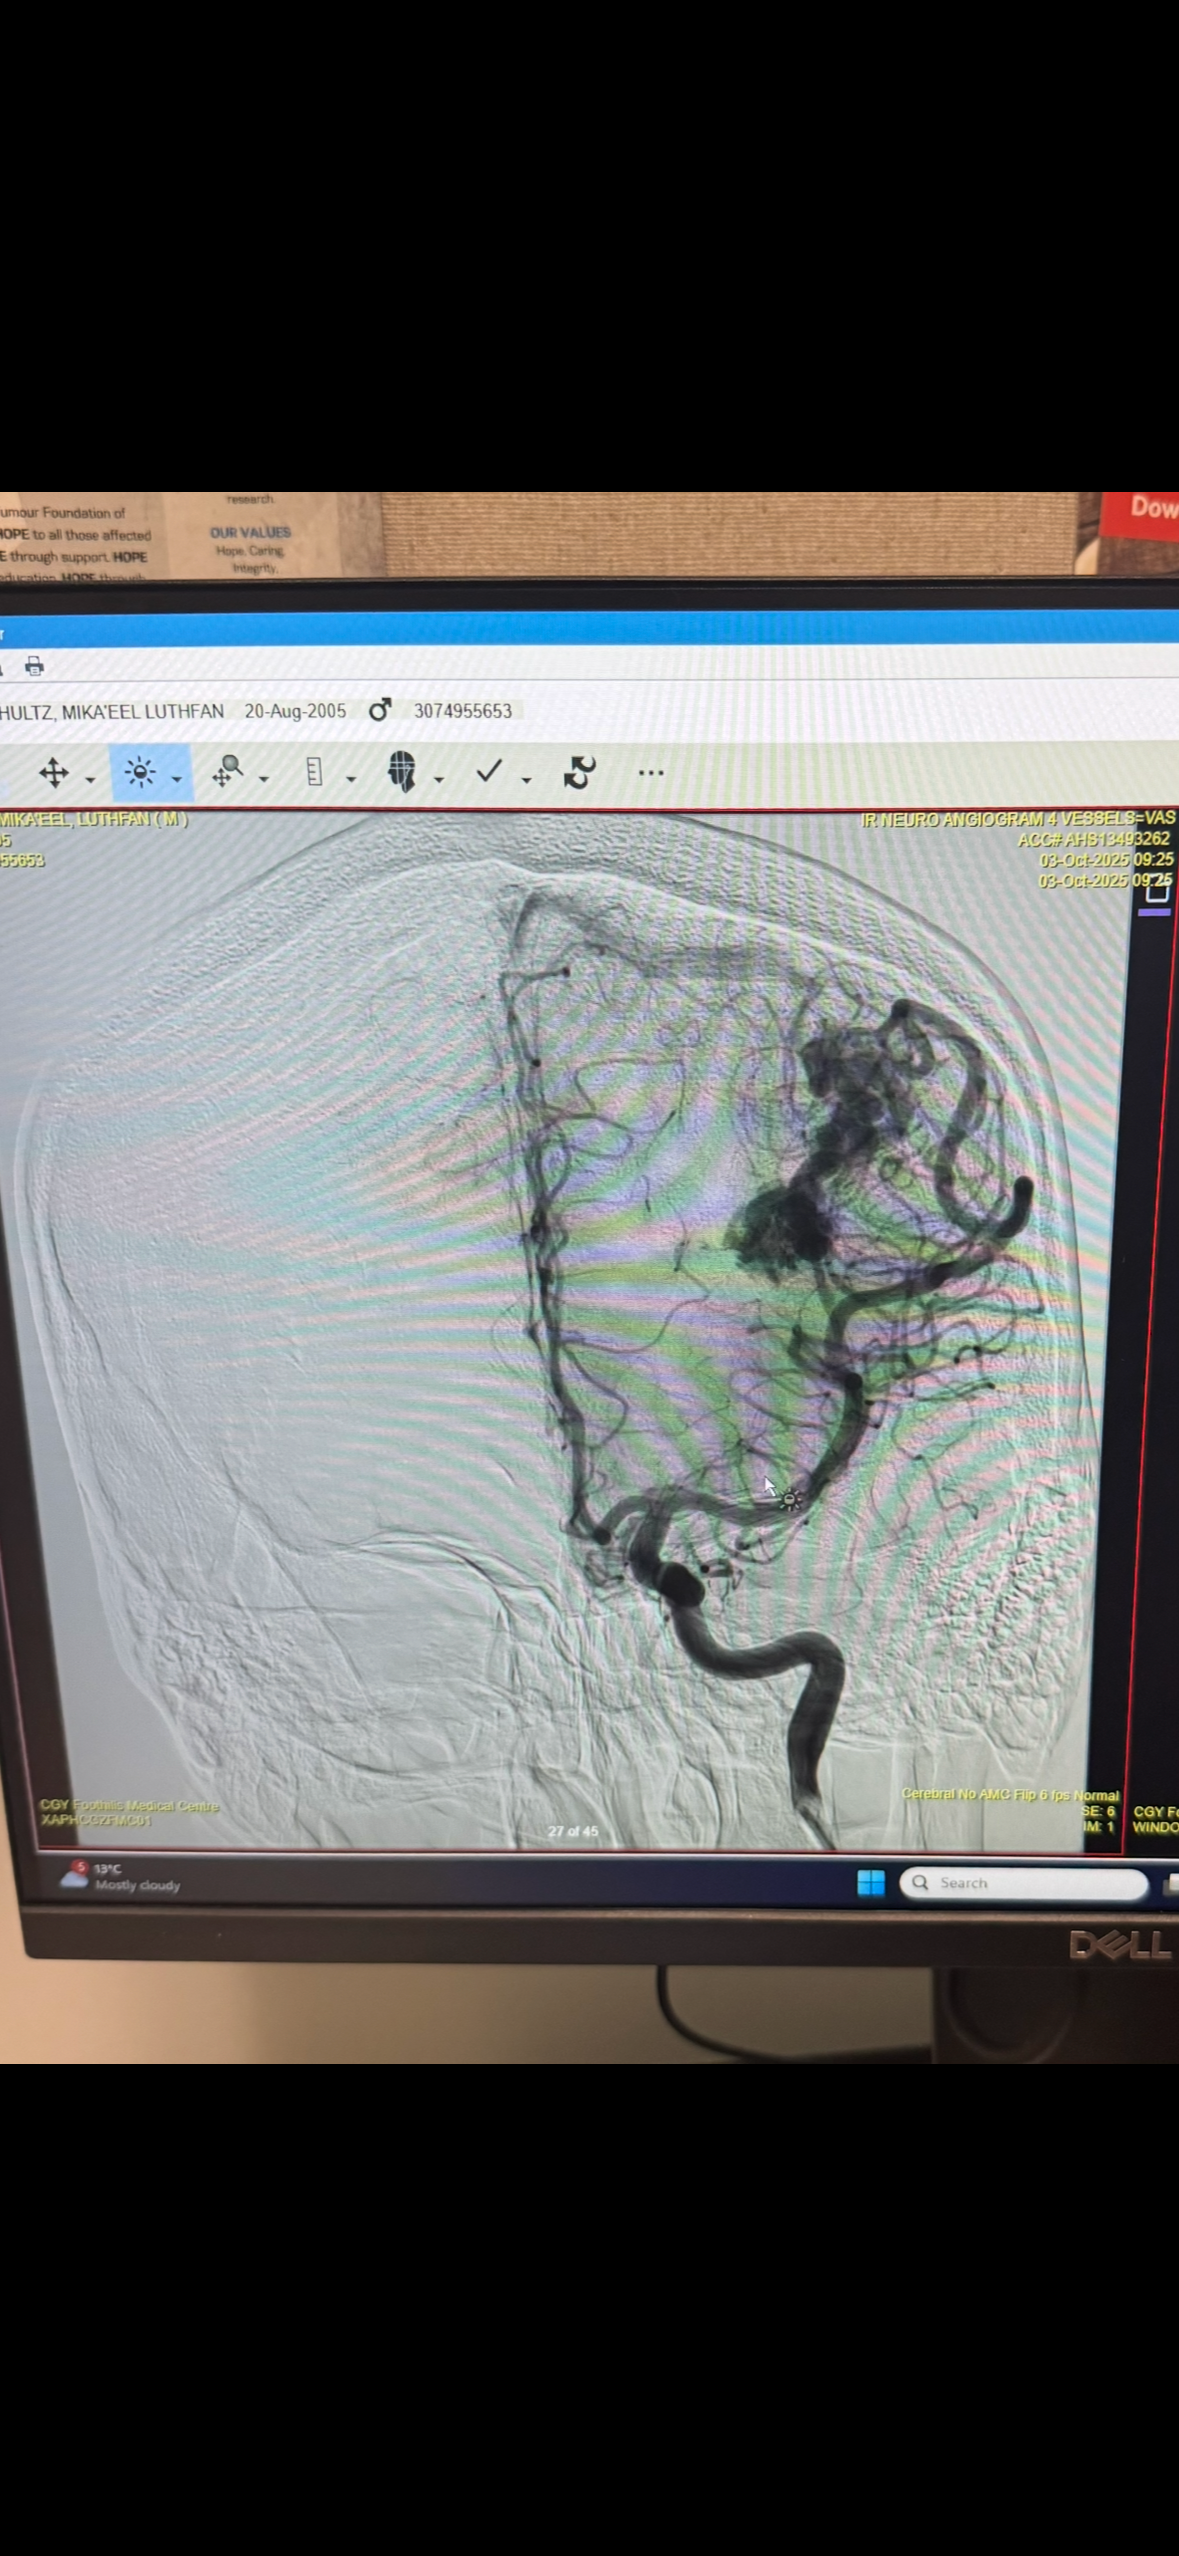

Hi, this is Cheryl Mcleish and Iam looking to raise funds for Mike Schultz. As some of you are aware, last October Mike suffered a brain bleed called a Arteriovenous Malformation or AVM.

The time has now come for him to undergo a long delicate brain surgery next week -November 26th. This surgery will be a permanent cure but comes with a 3 to 6 month recovery period. Mike must be off work to focus on rest and physical/cognitive therapy. I am looking for help to cover some of mikes living expenses, such as rent, groceries and car payments to relieve some financial stress.